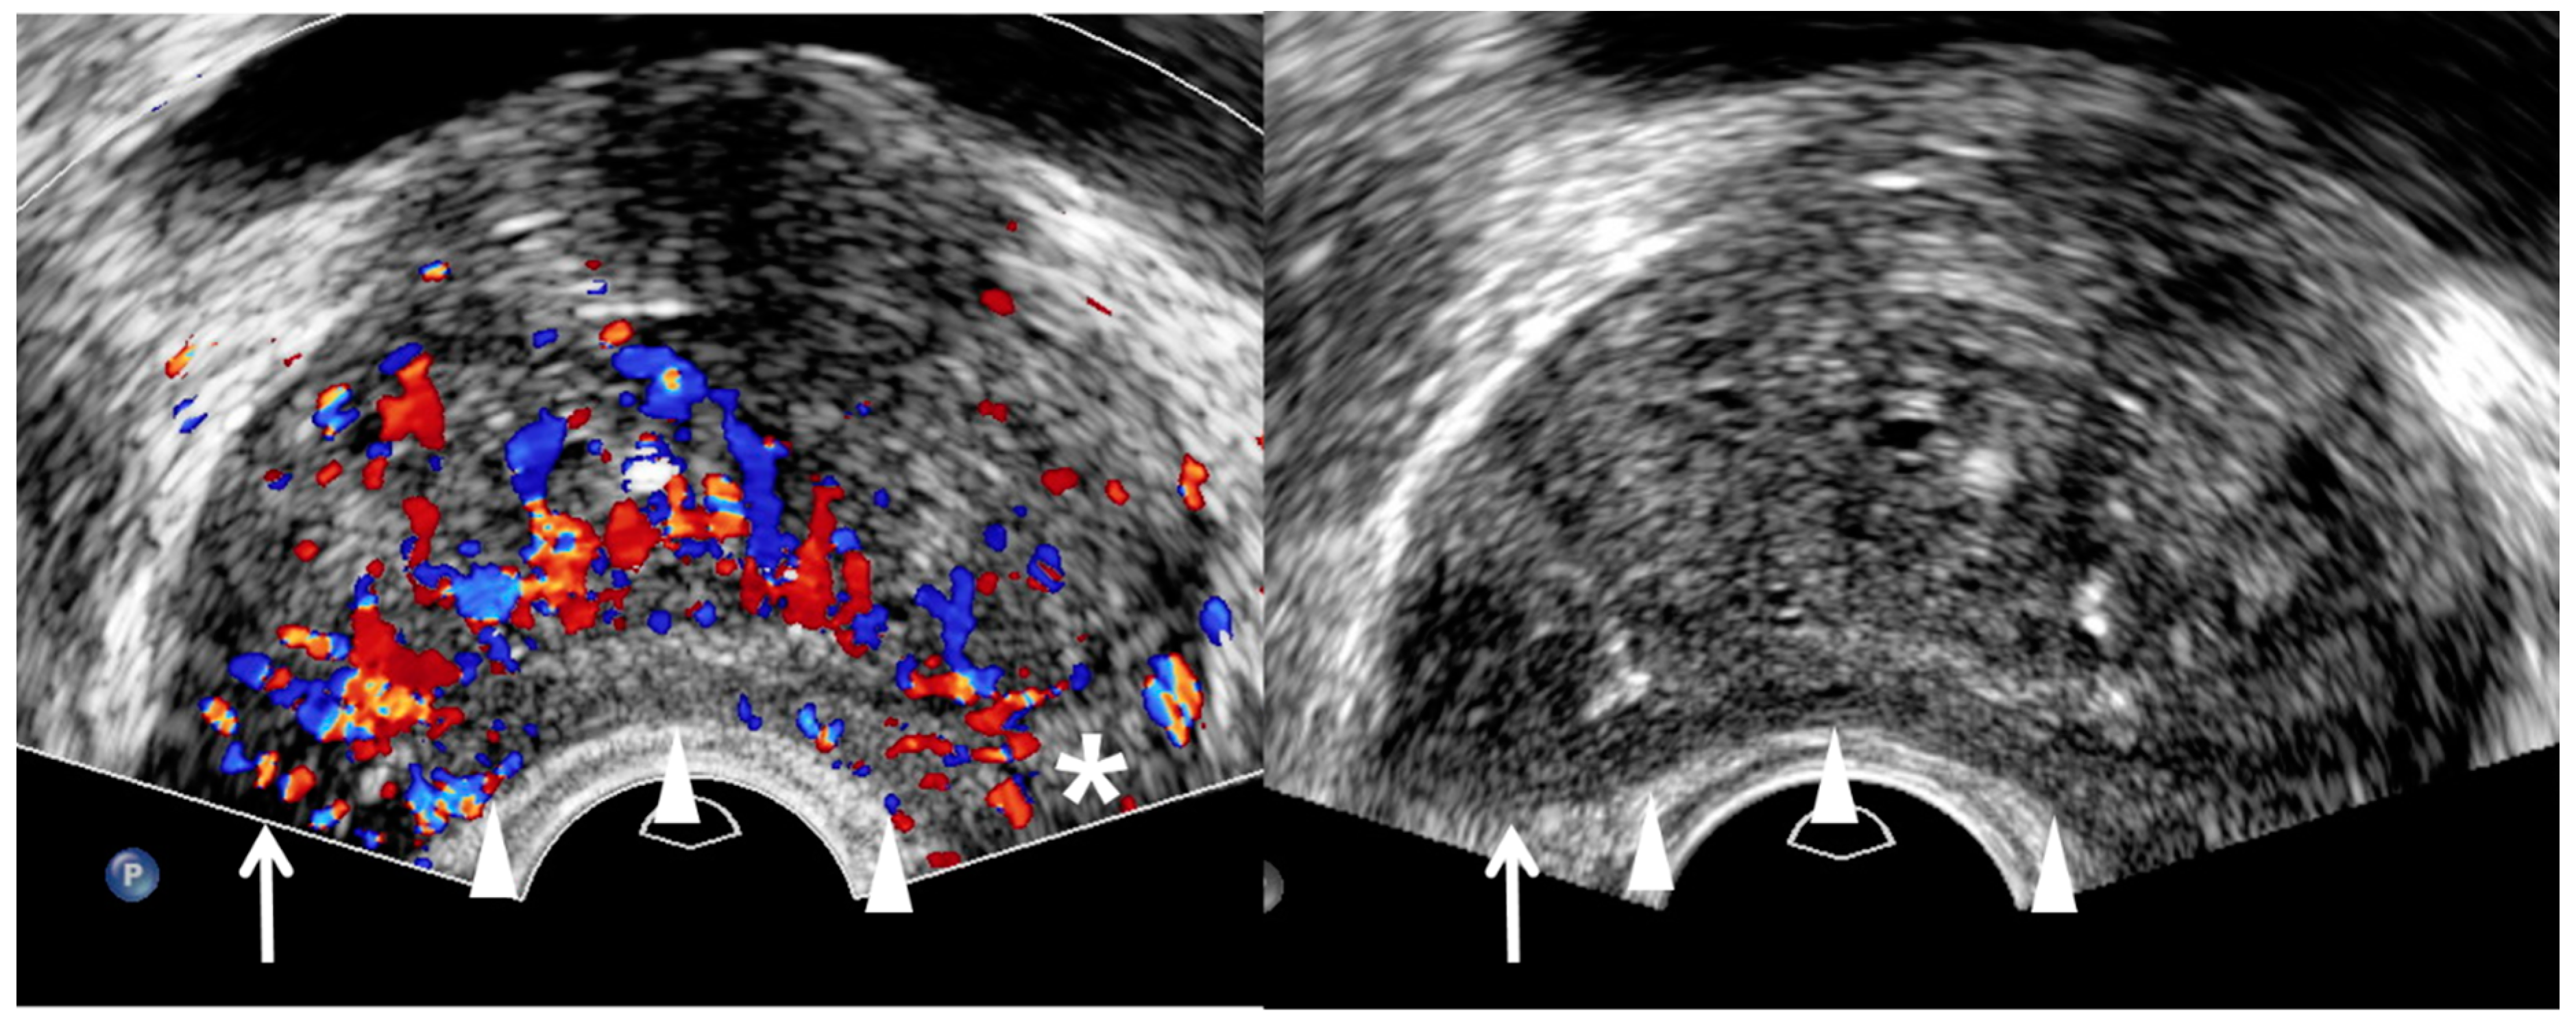

3. TRUS Imaging Features

| TRUS Features | Peripheral Cancer | Transition Cancer | ||

|---|---|---|---|---|

| Insignificant Cancer | Significant Cancer | Insignificant Cancer | Significant Cancer | |

| Echogenicity | Low | Lower | High | Higher |

| Size | Small | Large | Small | Large |

| Echotexture | Homogeneous | Heterogeneous | Homogeneous | Heterogeneous |

| Margin | Smooth | Irregular | Smooth | Irregular |

| Perfusion | Low | High | NA | NA |

| Hypoechoic rim | NA | NA | Clear | Unclear |